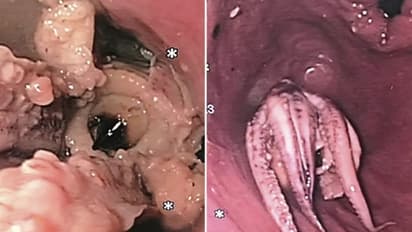

ഡോക്ടര്മാര് സ്കാൻ ചെയ്ത് നോക്കിയപ്പോള് തൊണ്ടയില് എന്തോ കനമുള്ള വസ്തു കുടുങ്ങിയിരിക്കുന്നതായി കണ്ടെത്തി. തുടര്ന്ന് ഇവര് എൻഡോസ്കോപ്പി ചെയ്യുകയായിരുന്നു. ഇതിലെ ക്യാമറയിലാണ് തൊണ്ടയില് എന്താണ് കുടുങ്ങിയതെന്ന് കണ്ടെത്തിയത്.

അത്താഴത്തിന് ഇദ്ദേഹം ഒരു റെസ്റ്റോറന്റില് നിന്ന് കഴിച്ച നീരാളിയാണ് തൊണ്ടയടച്ച് കുടുങ്ങിപ്പോയതത്രേ. അറിയപ്പെടുന്ന സീഫുഡ് വിഭവമാണ് നീരാളി. പുറംരാജ്യങ്ങളില് പലയിടങ്ങളിലും അത് വ്യാപകമായി ഭക്ഷണാവശ്യങ്ങള്ക്ക് ഉപയോഗിച്ചുവരുന്നതാണ്.

അബദ്ധത്തില് ഇത് ഒന്നിച്ച് കഴിച്ചതോടെ ഇദ്ദേഹത്തിന്റെ തൊണ്ടയില് കുടുങ്ങിയതാണത്രേ. ഭക്ഷണം തൊണ്ടയില് കുരുങ്ങിയാല് നേരത്തെ സൂചിപ്പിച്ചത് പോലെ ശ്വാസതടസം നേരിട്ടാണ് മരണം സംഭവിക്കുന്നത്. അതിനാല് തന്നെ ഇത്തരം സംഭവങ്ങളില് നിന്ന് അറിവുള്ക്കൊണ്ട് ഇക്കാര്യങ്ങള് ശ്രദ്ധിക്കണമെന്നതാണ് വിദഗ്ധര് സൂചിപ്പിക്കുന്നത്. കേസ് സ്റ്റഡിക്കൊപ്പമുള്ള ഫോട്ടോകളും വളരെയധികം പങ്കുവയ്ക്കപ്പെടുന്നുണ്ട്.